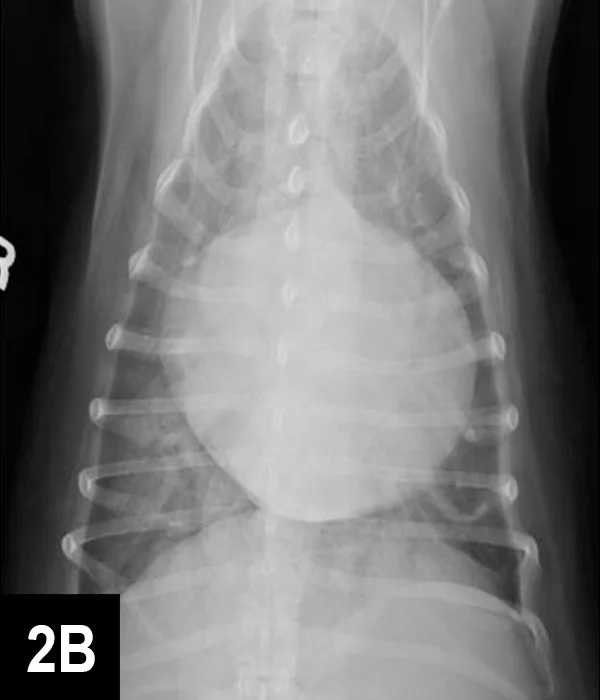

FIGURE 2A

Right lateral thoracic radiograph

A murmur and regular rhythm were auscultated. The heart rate was approximately 180 bpm, and crackles were auscultated in the caudodorsal lung fields. A 6 lead electrocardiogram (ECG, Figure 1) and thoracic radiographs (Figure 2A and 2B) were performed.

A sinus rhythm (HR is ~150 bpm) and left ventricular enlargement pattern were noted on ECG: the sensitivity was decreased to 5 mm/mV, and R waves measured ~3 mV (upper end of normal R-wave height is 2.5 mV). Thoracic radiographs revealed severe left atrial enlargement with moderate left ventricular enlargement. There was a moderate interstitial to alveolar pulmonary pattern most pronounced in the caudodorsal lung fields, which is consistent with left-sided congestive heart failure resulting from degenerative mitral valve disease.